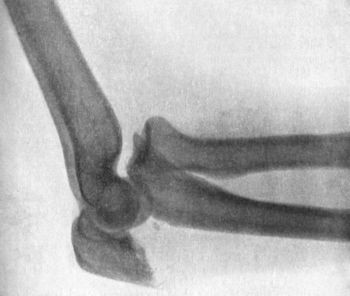

90 38.Radiogram of Incomplete Backward Dislocation of Elbow

91 39.Forward Dislocation of Elbow, with Fracture of Olecranon